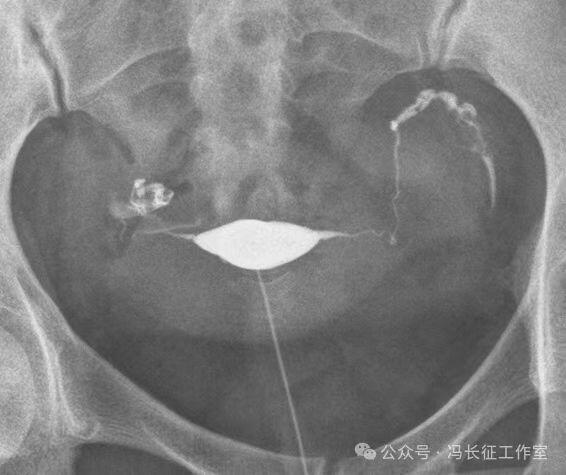

下面是一例正常子宫输卵管造影图(4张片)

微信图片_20240215160222.jpg